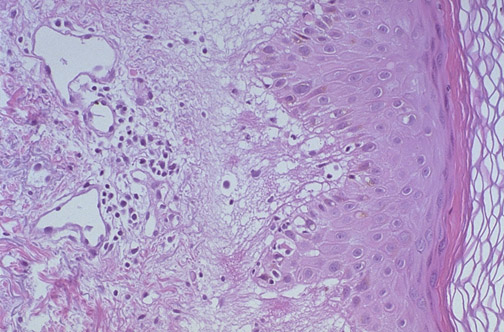

| At high magnification, the cytotoxic CD8 cell inflammatory reaction of erythema multiforme is characterized by epithelial cell necrosis at the dermal-epidermal junction. These lesions are "multiform" because macules, papules, vesicles, and bullae may be seen grossly, with symmetric involvement of the extremities. |